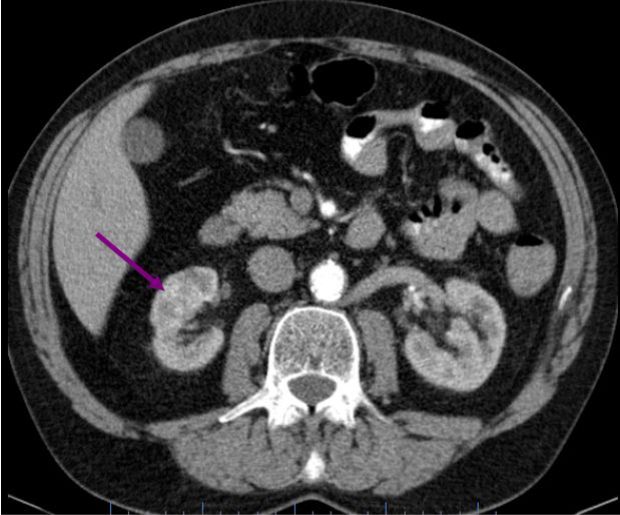

Muž 58 let – světlobuněčný karcinom

Na vyšetření přišel 58letý Jan Vokřálek, který byl předtím vyšetřen praktickým lékařem (PL). Pacient již 3 dny trpí trvajícím otokem pravé dolní končetiny, praktický lékař mu zjistil suspektní tromboflebitidu. Dále trpí dyspeptickým syndromem. Lumbalgií netrpí, hematurii neguje.